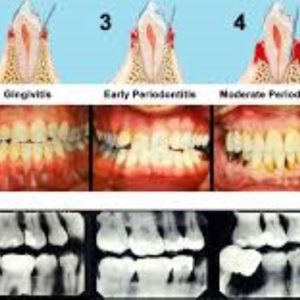

- Identify the oral manifestations of bulimia nervosa in adolescents, including dental erosion, dental caries, and soft tissue damage.

- Recognize the oral health risks associated with vaping in adolescents, such as gingival inflammation, xerostomia, and enamel erosion.